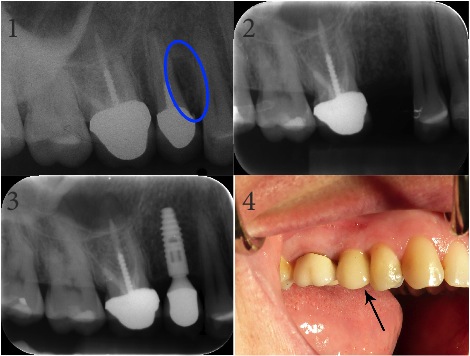

Endodontic & Implantology Associates Bone Grafting and Dental Implant Case Study: Case B

1. Fractured Tooth (Note: Lesion to surrounding bone area indicates fracture)

2. Extraction of Fractured Tooth and Bone Graft

3. Final X-Ray with Implant

4. Final Implant